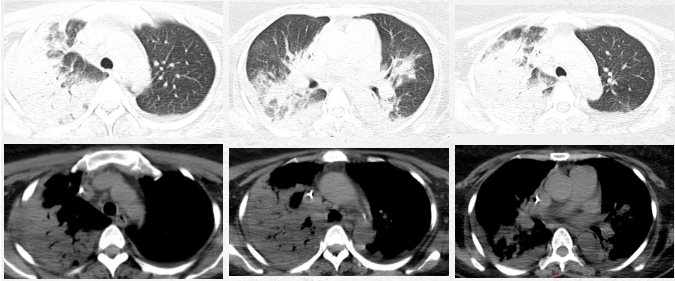

胸部CT显示

张阿姨肺上有大片严重的肺炎

接近一半都没有正常通气功能